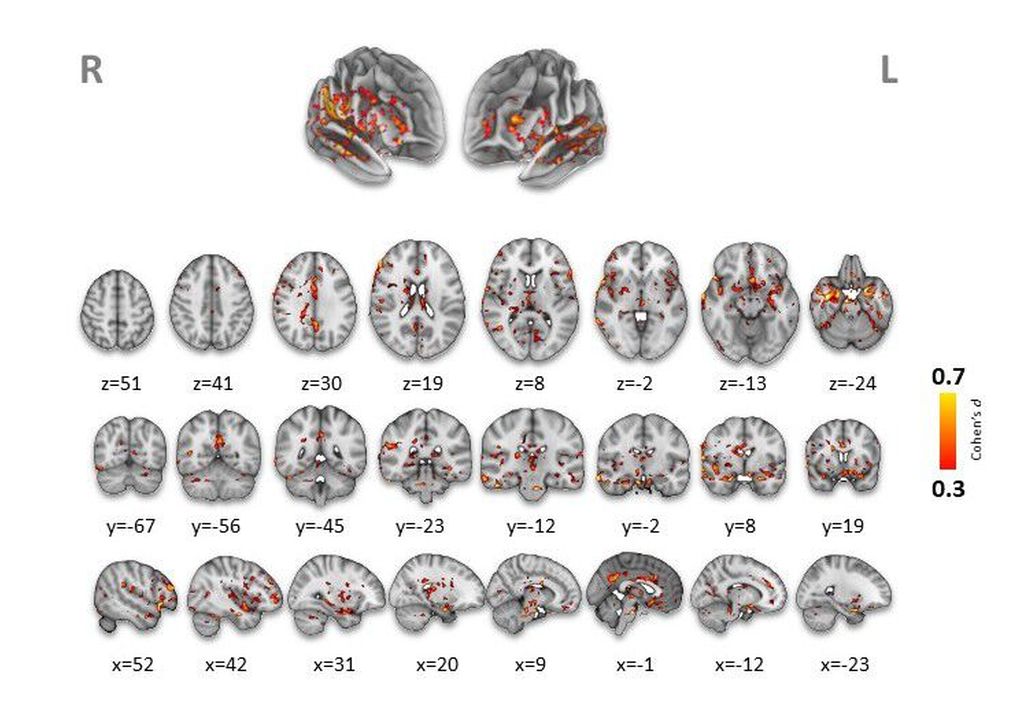

Der Gruppenvergleich ergab signifikant höhere Ktrans-Werte in der SSD-Gruppe im Vergleich zu den Kontrollen, nach Korrektur für Kovariablen wie Alter, Geschlecht, BMI, Bildung und Raucherstatus.

Am deutlichsten zeigte sich der Effekt im Thalamus, in der Amygdala, dem Hippocampus, dem Putamen, dem Cingulum, der Inselrinde sowie in frontalen und temporalen Kortexarealen – Regionen, die bereits in früheren SSD-Studien als zentral für strukturelle und funktionelle Veränderungen beschrieben wurden.15 Damit bestätigt die LMU-Studie die bislang einzige DCE-MRT-Studie an Menschen mit SSD von Cheng et al., die 2019 erhöhte Thalamus-Leckagen bei 29 Patient:innen beschrieb – und erweitert die Befunde auf zusätzliche Regionen möglicherweise dank größerer Stichprobe und längerer Scanzeit.

Abb. 1: Der Vergleich der BHS-Permeabilität (Ktrans) zwischen den beiden Kohorten zeigt eine deutlich erhöhte, weitverbreitete Leckage bei Personen mit SSD im Vergleich zu gesunden Kontrollen. Die farbigen Signale markieren Hirnvoxels, in denen in der SSD-Gruppe eine statistisch signifikant höhere Durchlässigkeit (statistische Schwelle: voxelweise p<0,001; FWE-Cluster-korrigiert p<0,05, hier Cohen’s d zwischen 0,3 und 0,7) nachgewiesen wurde. Die Volumenbilder sind in axialer (z), koronaler (y) und sagittaler (x) Orientierung mit den standardisierten MNI-Koordinaten gezeigt. Hinweis: radiologische Konvention, L = R und R = L